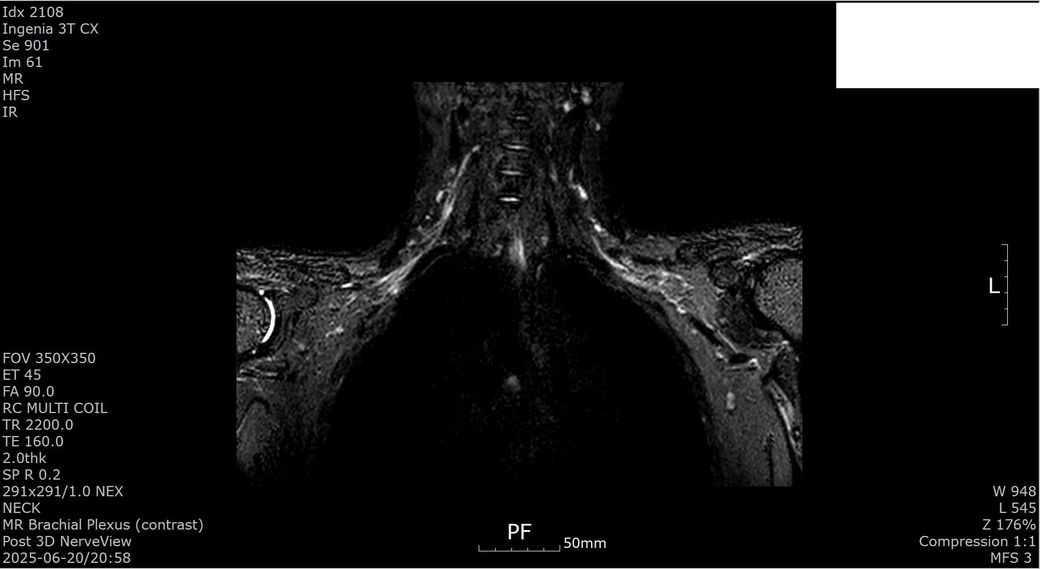

[상완신경총 brachial plexus] mri 판독 부탁드립니다

2025년 1월경 흉곽출구증후군(우측 사각근 유리술, 우측 제1늑골 제거술, 우측 상완신경총 박리술) 수술한 뒤 5개월 지난 2025년 6월경 상완신경총 mri 검사했습니다.